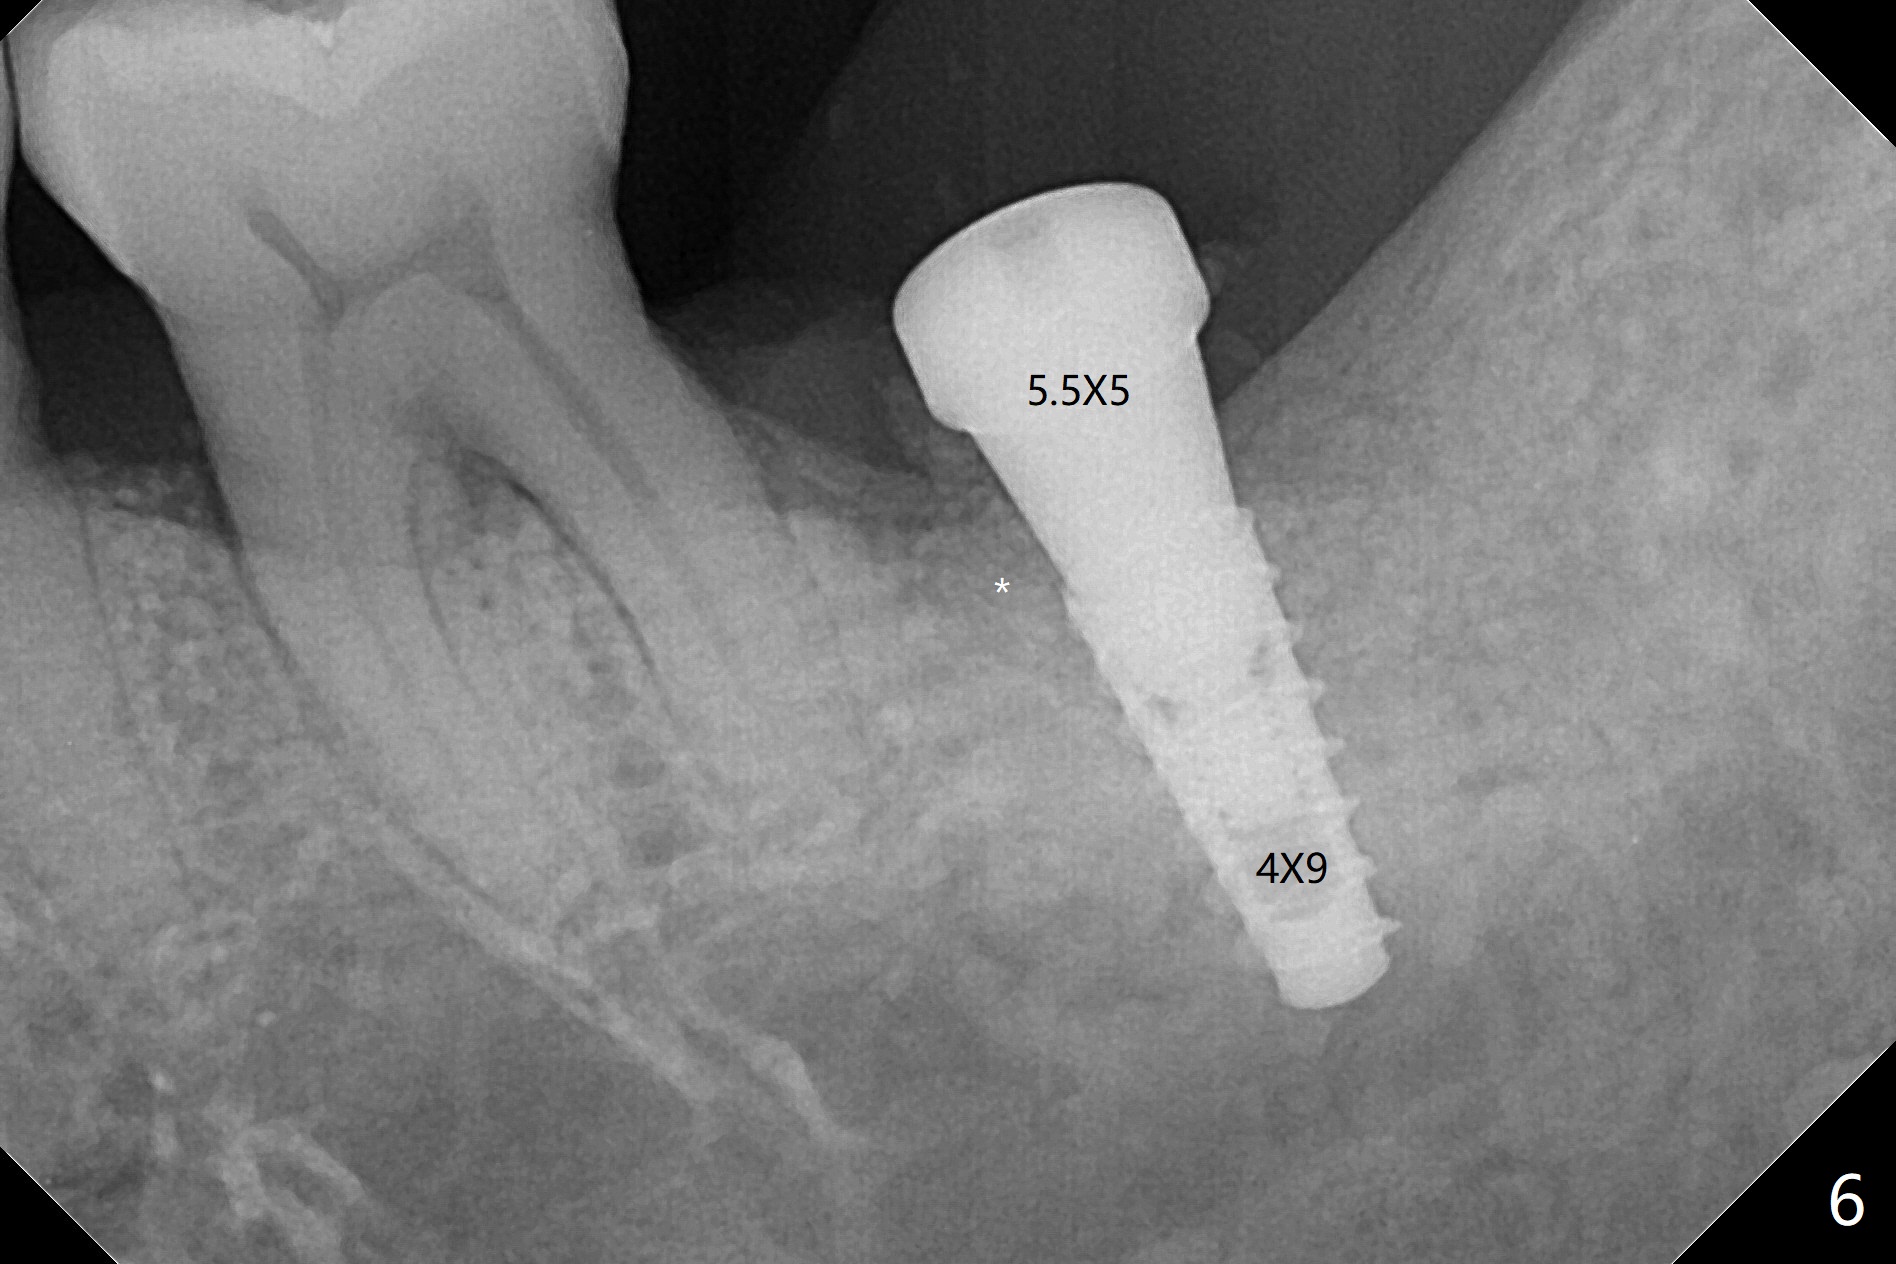

导板种植是否需要切开取决于牙槽嵴角化龈宽度,放置导板后,插入环形刀(图一),用手的压力(不要开手机)接触牙龈后,抽出环形刀,并且取出导板,检查环形标记是否累及颊侧粘膜(图二)。这个病例没有,所以没有切开,也没有保留角化龈(骨质硬,预计术后可以使用愈合基台)。在34毫克利多卡因17微克肾上腺素浸润(jinrun)麻醉下,完成钻洞(最后钻头3.5x10毫米),植体植入,拍摄CT却发现植体非常接近神经(图三,五),似乎钻洞向舌侧偏移(与设计(图四)对比),可能与没有远中牙齿固位有关。由于术中没有疼痛,估计没有直接损伤神经,放置愈合基台,在后者周围空间塞入骨粉(图六:*)。理想情景使用2.2x7.3毫米钻头后,拍摄CT,最后植入4.5或者5.0x7.3毫米植体(图五')。术后没有疼痛也没有麻木。